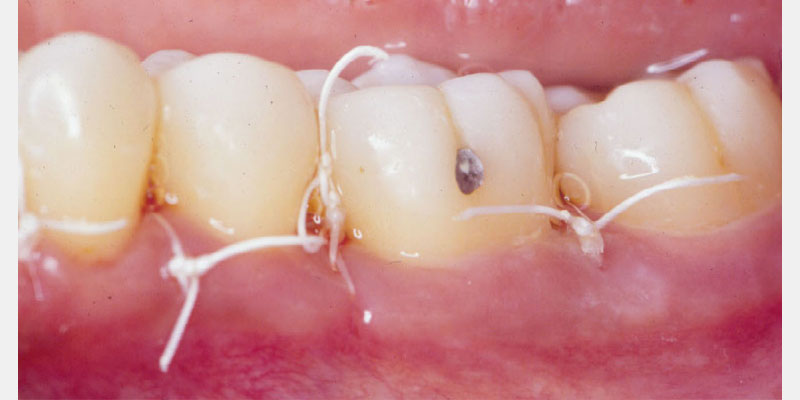

Periodontal defects include the intrabony and furcation-type defects, as well as with gingival recession or loss of attachment. The periodontal literature validates the regenerative potential of biologically active bone replacement grafts (Figs. 1–5).5, 6, 7 Periodontal regeneration with histological evidence of new cementum, periodontal ligament and alveolar bone has been shown in the human model with a recombinant growth factor and a porcine (pig)-derived protein.8, 9, 10

Histologic evidence from a recent study shows that regeneration can be achieved with rhPDGF-BB, β-TCP, and collagen in gingival recession-type defects.12 Gingival recession defects have been treated successfully with rhPDGF, β-TCP and a collagen membrane with a root coverage technique (Figures 6–7). This technique was compared to a subepithelial connective tissue graft within a case series,13 and more recently in a controlled clinical trial. The comparisons demonstrated that the growth factor technique was comparable to the others for root coverage outcomes.14 Many studies validate the use of EMD for periodontal and mucogingival defects.5, 6, 15 The histological article on EMD offers proof of principle for incredible quantities of true periodontal regeneration.16